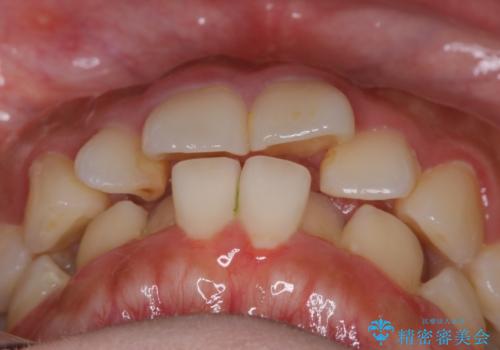

【非抜歯】インビザラインでガタつきと口元を改善!非抜歯でも印象が変わる矯正治療

- 歯のガタつきと口元の突出感を主訴に来院されました。

装置の希望がインビザラインだったため、非抜歯でインビザラインの特徴を最大限に生かして行う矯正治療を選択しました。

一般的に口元を下げるための治療というと抜歯矯正を思い浮かべる方が多いかと思います。そもそもガタつきを治したり歯を引っ込めるためのスペースの作り方には大きく分けて4種類の方法があります。

①抜歯 ②歯列の幅の拡大 ③IPR(歯の幅を削って小さくする) ④歯の後方移動 です。

インビザラインの登場により抜歯以外の3種類の方法を効率よく活用することができるようになりました。

そのため、非抜歯でも口元の環境が改善するケースがあります。